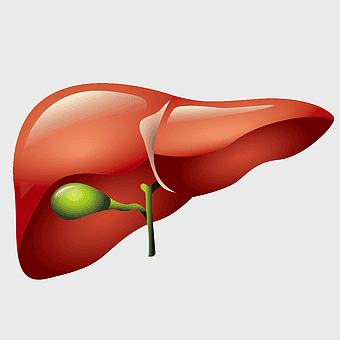

human liver anatomy, medical imaging liver, liver radiology scan, human digestive system liver, abdominal organ visualization, internal anatomy illustration, liver health diagram -

liver illustration, human liver cartoon, cartoon liver image, liver organ diagram, liver anatomy visual, medical liver graphic, liver health depiction -

human liver anatomy, liver disease symptoms, bile production process, liver function tests, digestive health illustration, organ detoxification, gastrointestinal health benefits -

liver with gallbladder diagram, human liver function, bile production organ illustration, digestive system anatomy, liver and bile duct visual, human anatomy medical graphic, hepatology reference image -